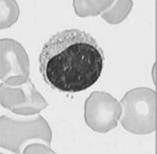

. Linfócitos (fig7) – Agranulócitos com núcleo esférico e volumoso, constituem cerca de 30 % de todos os leucócitos (1500 a 3000/mm3). A maioria dos linfócitos pertence a um dos seguintes grupos: linfócitos B ou linfócitos T. Os linfócitos B, quando activados diferenciam-se em plasmócitos, que produzem anticorpos, e em células de memória. Os linfócitos T contribuem para a activação dos linfócitos B e destroem agentes patogénicos. Considera-se ainda a existência de um terceiro grupo de linfócitos – células NK (natural killer cells) que têm como função destruir células infectadas por vírus e células cancerosas.

Fig7. Linfócitos